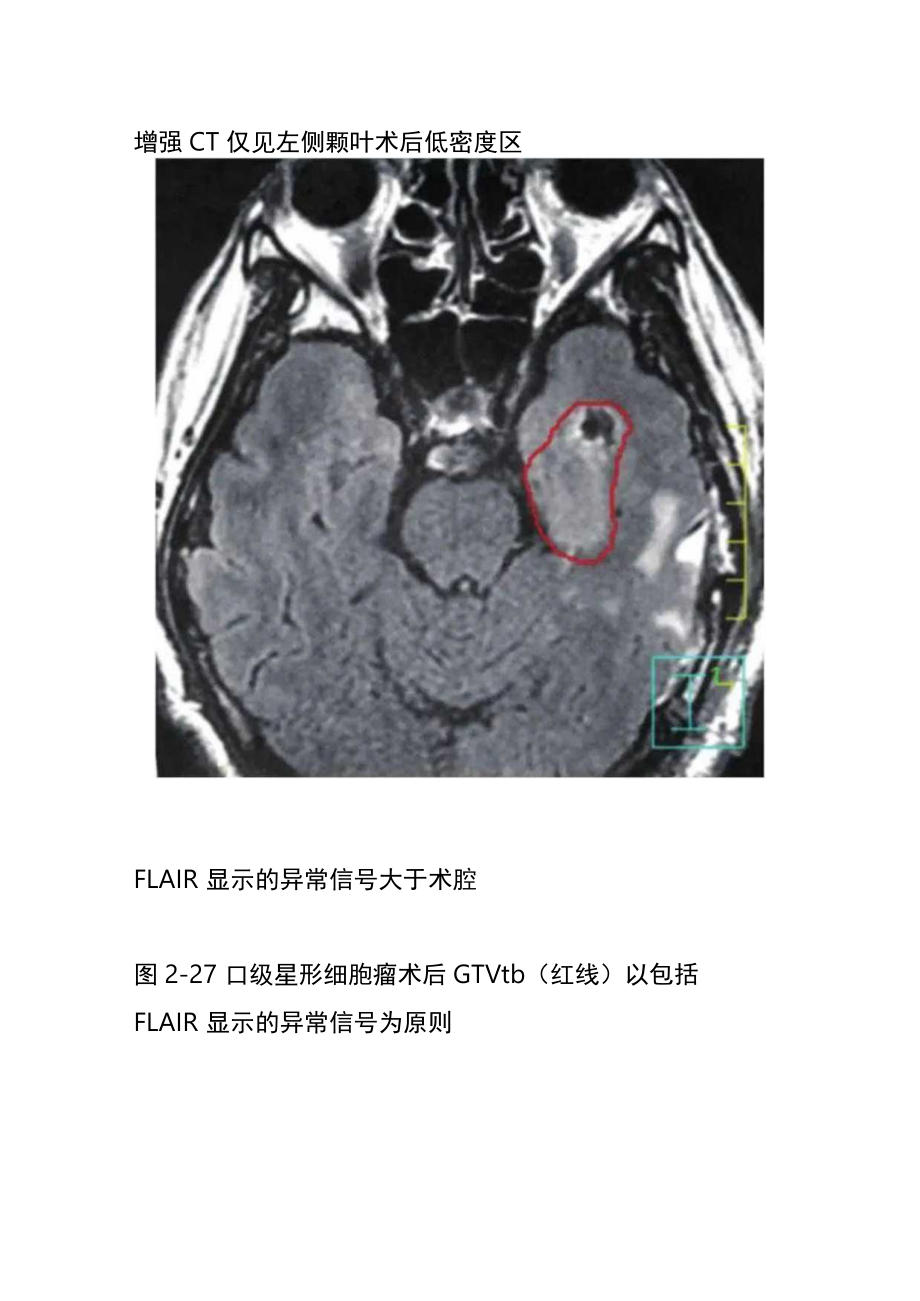

1、胶质瘤放疗靶区勾画一、低级别胶质瘤低级别胶质瘤影像上一般无增强,其肿瘤具体位置一般在MRI的T2FLAIR像上表现为异常信号,因此术后GTV瘤床的勾画原则是将T2FLAIR显示的异常部分作为GTVtb对待(图2-27、图2-28)o增强CT仅见左侧颗叶术后低密度区FLAIR显示的异常信号大于术腔图2-27口级星形细胞瘤术后GTVtb(红线)以包括FLAIR显示的异常信号为原则图2-28少突胶质瘤(II级)术后GTVtb(红线)的勾画以T2FLAIR显示的异常信号为原则,黄线为外扩1.5cm的CTV而CTv一般根据分化程度而有所不同:病理分化为I级者,CTV=GTV+1cm(即在GTV基础上外放